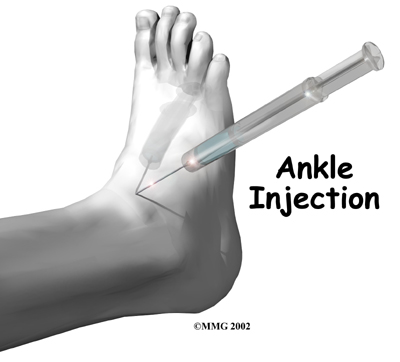

An injection of cortizone into the joint can give temporary relief from symptoms of OA. Cortisone is a powerful anti-inflammatory medication. When injected into the joint itself, cortisone can help relieve the pain. The pain relief is temporary and usually only lasts several weeks to months. There is a small risk of infection with any injection into a joint, and cortisone injections are no exception.

An injection of cortizone into the joint can give temporary relief from symptoms of OA. Cortisone is a powerful anti-inflammatory medication. When injected into the joint itself, cortisone can help relieve the pain. The pain relief is temporary and usually only lasts several weeks to months. There is a small risk of infection with any injection into a joint, and cortisone injections are no exception.

There are also new injectable medications that lubricate the arthritic joint. These medications have been studied mainly in the knee. It is unclear if they will help the arthritic ankle joint. These injectable medications are not usually prescribed for this condition yet.